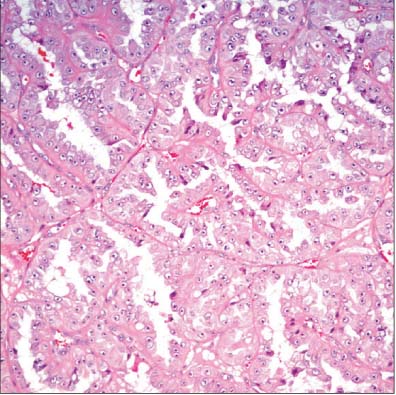

Fig. 2

Thyroid-like follicular carcinoma of kidney. Thyroid-like microfollicles are filled with colloid-like material (H&E, 200).